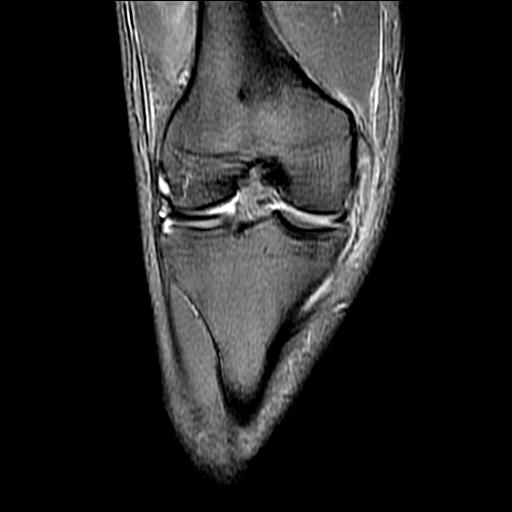

40岁男性,右膝关节外伤,x光平片示,髁间隆突撕脱骨折。

1、前交叉韧带撕裂;

2、外侧半月板后角撕裂;

3、关节腔积液。

前交叉韧带撕裂,关节腔积液.

半月板1-2级损伤   前交叉韧带撕裂伤   关节腔少量积液  诸骨未见新鲜外伤性改变

髁间隆突撕脱骨折;内侧副韧带损伤。

1、内侧副韧带撕裂;

2、前交叉韧带撕裂;

3、滑膜炎伴关节腔积液。

内侧副韧带撕裂及关节腔积液是肯定的,但是前交叉撕裂确定吗?会不会有容积效应的因素,因为前一张前交叉显示清楚,连续性良好,且较光滑。请问楼主有关节镜支持吗?我们医院也经常有这样的患者,但苦于没有关节镜,而无法对照、证实(除非完全断裂),出现了不同的诊断结果只能毫无意义的争论。

1、前交叉韧、内侧副韧带撕裂;

3、关节腔积液。4、髁间脊撕脱骨折。